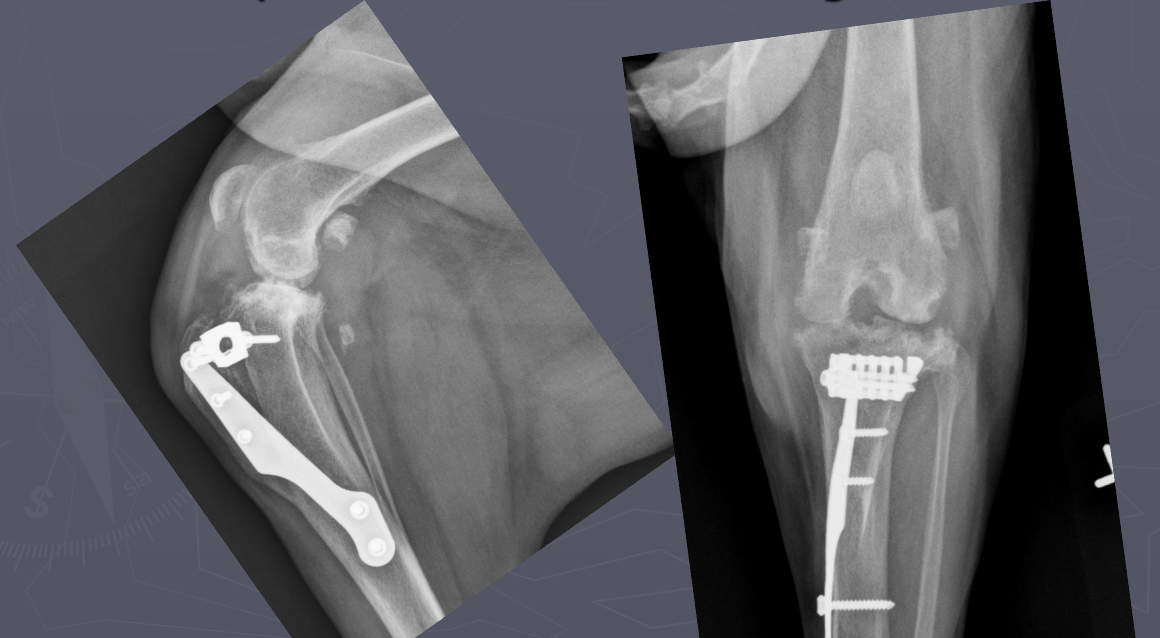

Q

What is shown in these radiographs?

A

dystrophic mineralization at the site of previous injection